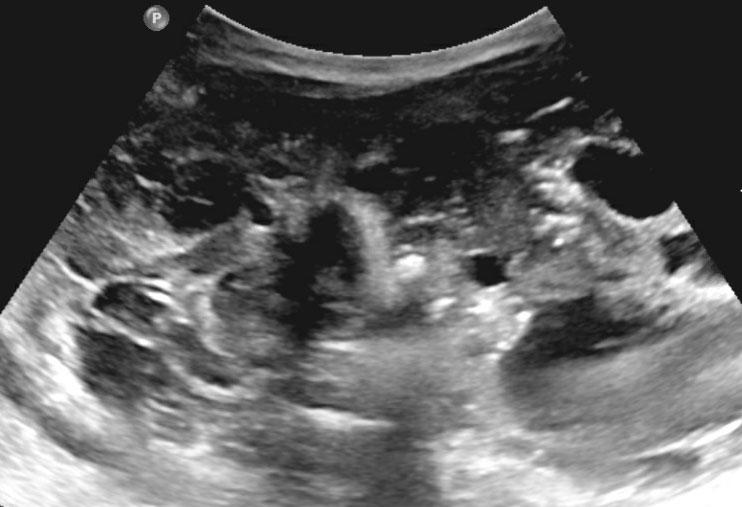

Siêu âm của một bé trai mười lăm tháng tuổi, ban đầu được nghi ngờ có khối u ở thận trái.

Siêu âm cho thấy một khối u nằm kề cực trên phía trong của thận trái. Khối u có vẻ tách biệt với thận. Khối u rất không đồng nhất và có nhiều vôi hóa.

Những phát hiện này phù hợp với u nguyên bào thần kinh hơn là u nguyên bào thận.